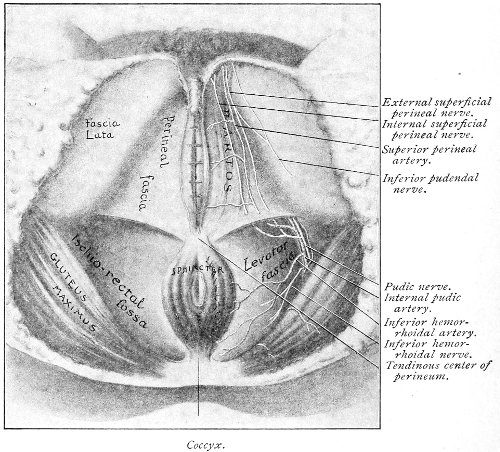

An accurate knowledge of the anatomy and mechanism of the female perineum is essential to an understanding of the nature and treatment of injuries to this structure. The anatomical structures lying between the anus behind and the symphysis pubis in front are those that most directly interest the gynecologist. Proceeding from 57 below upward, we find the following structures lying in superimposed planes: the skin, the superficial fascia, the deep layer of the superficial fascia, the transversus perinæi and the sphincter vaginæ muscles, the anterior layer of the triangular ligament, the posterior layer of the triangular ligament, the levator ani muscle (Fig. 19).

Fig. 18, A.—Superficial structures of the female perineum (Weisse).

Fig. 19.—Dissection of female perineum: on the left side the perineal muscles are exposed by the reflection of the perineal fascia; on the right side the muscles and the superficial layer of the triangular ligament have been removed, thereby exposing the deep layer of the ligament. S. V., Sphincter vaginæ muscle.

The vagina passes through these structures. They surround and support the ostium vaginæ as the fascia and muscles surround and support the opening of the rectum or the anus. The muscles and fasciæ are attached in the median line between the anus and the vagina, and therefore this part of the body, which is called the perineum, is supported or maintained in its 58 proper position by these various structures. The transversus perinæi arises from the ramus of the ischium and is inserted in the perineum. The bulbo-cavernosus, or sphincter vaginæ, arises in the perineum and is inserted in and about the clitoris. The inner fibers of the levator ani arise from the symphysis pubis and are inserted in the perineum and the lower part of the vagina (Fig. 20). When these muscles contract, their action, therefore, is to draw the perineum upward and forward. At the same time the anus is drawn upward and forward, and so also is the posterior margin of the ostium vaginæ and the lower portion of the posterior vaginal wall.